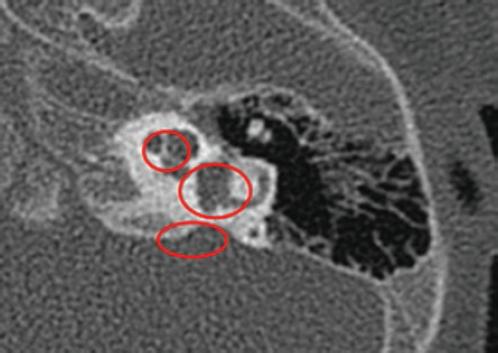

Figura 2 Gusher moderado. Oído izquierdo (corte axial) con las vueltas media y apical de la cóclea que confluyen, vestíbulo dilatado y acueducto vestibular ensanchado (partitura incompleta tipo II).